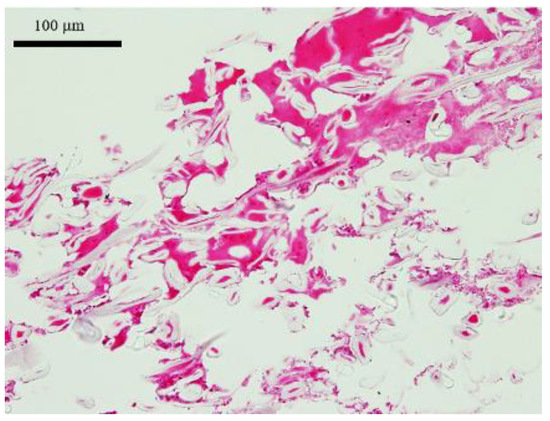

3.1. HE Staining of the Artificial Dermal Scaffold